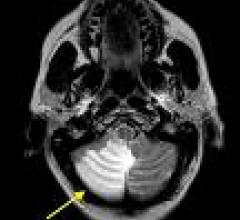

Interventional radiology uses tools like angiography X-ray systems to provide minimally invasive medical diagnosis and treatment using images.